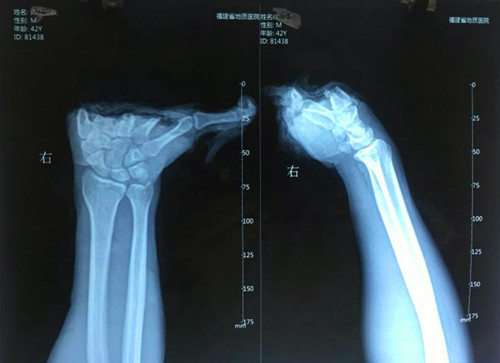

患者,许某某,男性,42岁,长乐某工厂职工,因在做工时被机器绞伤,右手掌完全离断。经诊断分析:手部掌骨粉碎,血管、神经、肌腱、肌肉、皮肤绞烂撕脱,伤情严重,再植难度大,手术时间长。

患者入院后,在骨科郑国钦主任带领下,积极完善术前准备后,第一时间为患者在麻醉下行“断掌清创探查再植”手术,术中固定粉碎的骨块,重建屈、伸指肌腱功能。在显微镜下探查血管、神经,发现主要血管撕脱伴管壁碎裂、管腔内栓塞,术中予移植多根血管,修复离断掌体的供血动静脉,同时修复断裂的神经。术中力排各种困难与风险,医护人员经过长达12小时的协同奋战,当松开患者右上臂气囊止血带后,患者离断的右手掌皮肤瞬间由苍白转为红润。当再植手术成功告知患者及家属手术顺利时,他(她)们担心忧愁的脸上均露出了宽慰的笑容。